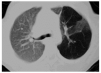

En la TAC torácico helicoidal en inspiración y espiración forzada, se apreció una hiperclaridad del lóbulo superior izquierdo con disminución de la vascularización pulmonar. No se evidenciaron signos de obstrucción bronquial ni de atresia (figs. 3 y 4).

Figura 3.--TAC Pulmonar en inspiración forzada.

Figura 4.--TAC Pulmonar en espiración forzada.

La TAC pulmonar muestra la destrucción del parénquima pulmonar afecto, más evidente en la espiración forzada, pudiendo acompañarse o no de broquiectasia12. Además la arteria pulmonar del pulmón patológico suele tener disminuido su calibre y, en consecuencia, el flujo sanguíneo pulmonar se reduce.